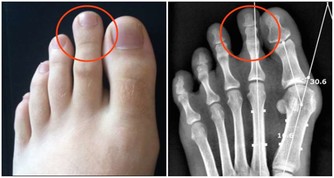

因此,對中、老年人突然逐漸加重的肩臂痛,無論是否伴有呼吸道症狀,

且肩臂痛經牽引或止痛藥治療,只能暫時緩解症狀而不能阻止疼痛進行性加重時,就需高度警惕。

應及時到醫院做檢查,以免誤診。